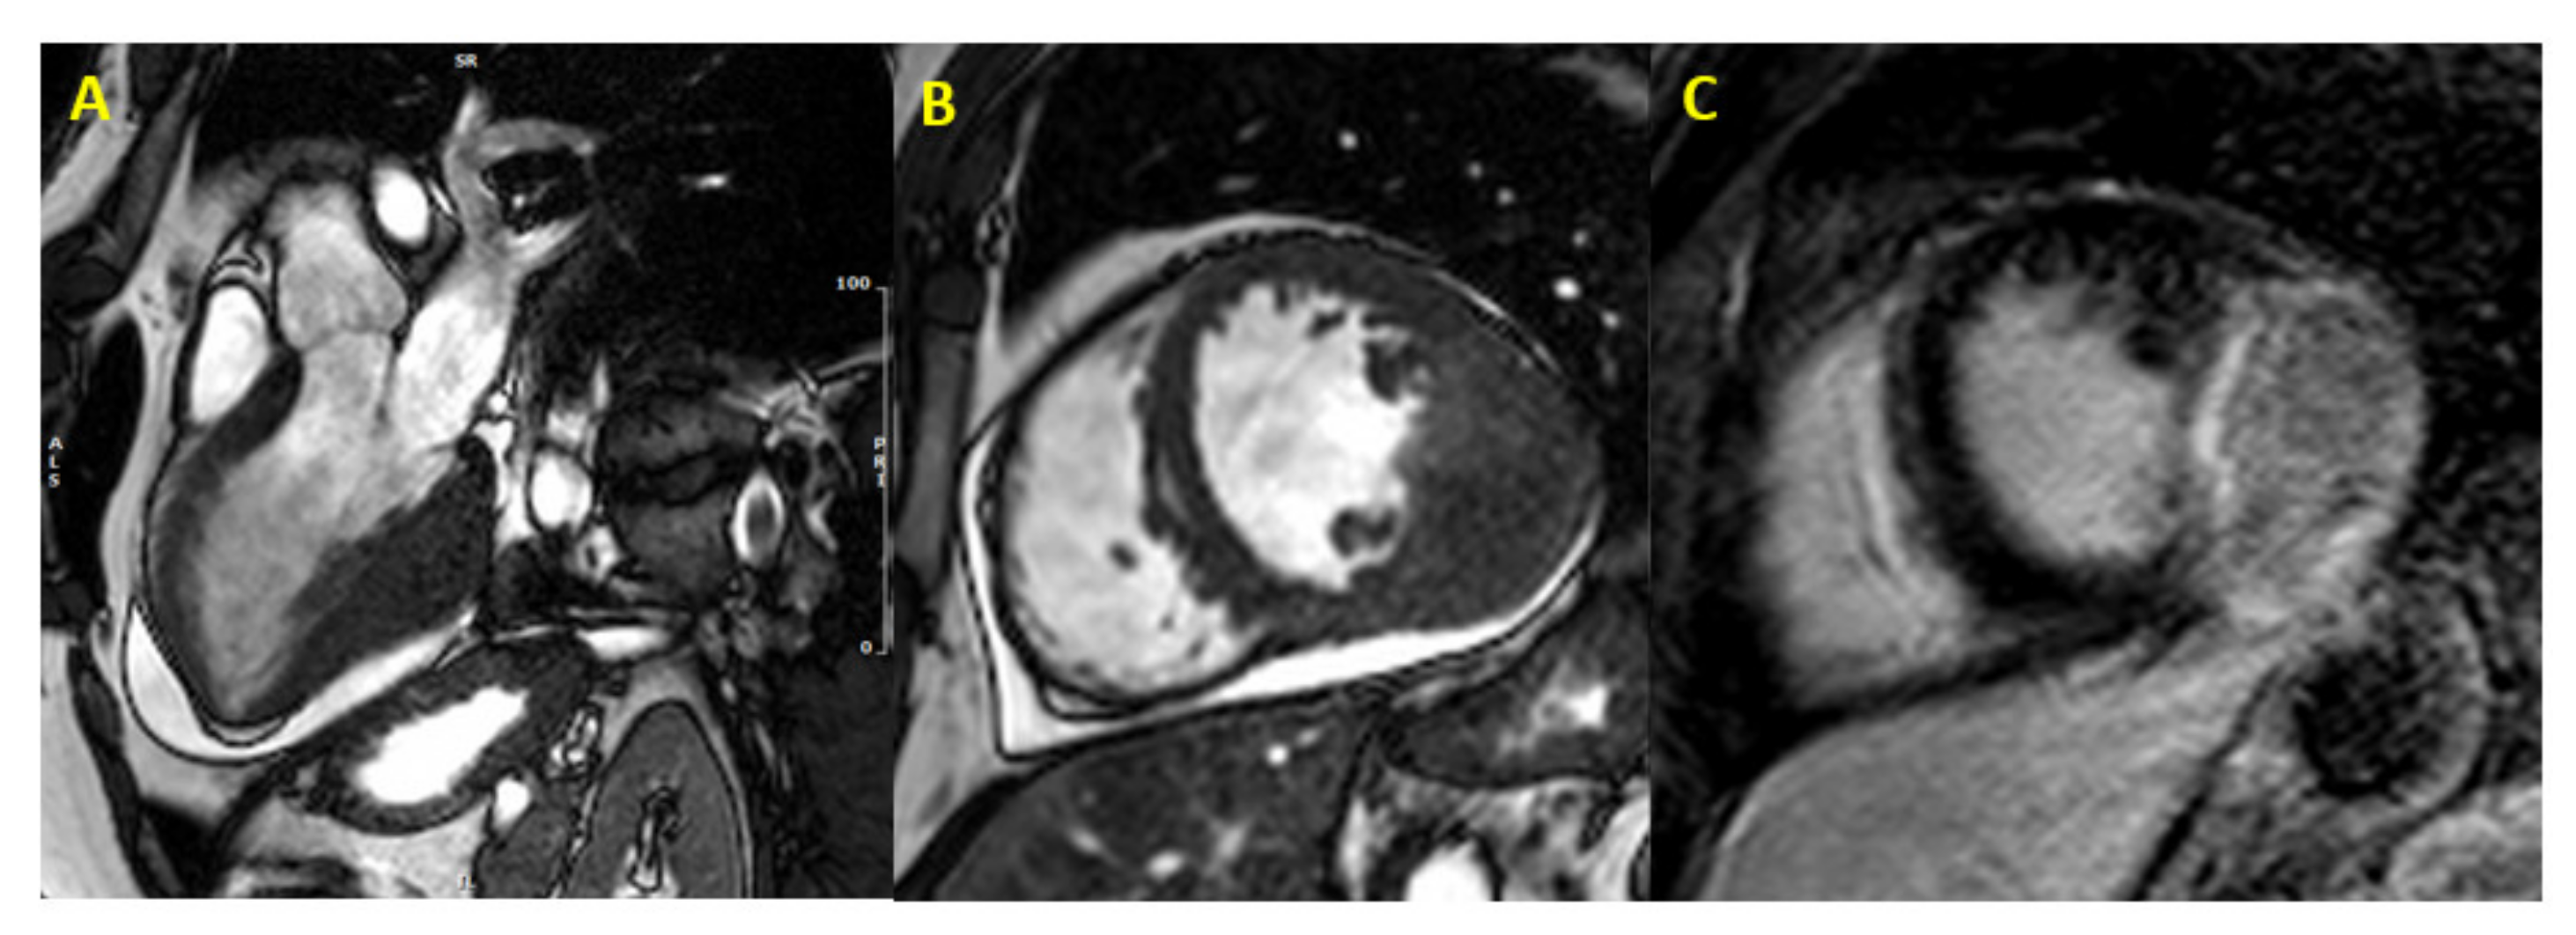

| Hamartoma of mature cardiac myocytes | Ventricle | Enlarged, highly disorganized cardiomyocytes | T1 Isointense T2 inhomogeneously hyperintense | Very similar to HCM | [18,19] |

| Cardiac fibroma | Ventricle and ventricular septum | Tumor cells resemble fibroblasts, calcification is common | T1 and T2 hypointense, heterogeneous late contrast enhancement with hypoenhancing core | Found in 3% of patients with Gorlin syndrome | [20,21,22,23] |